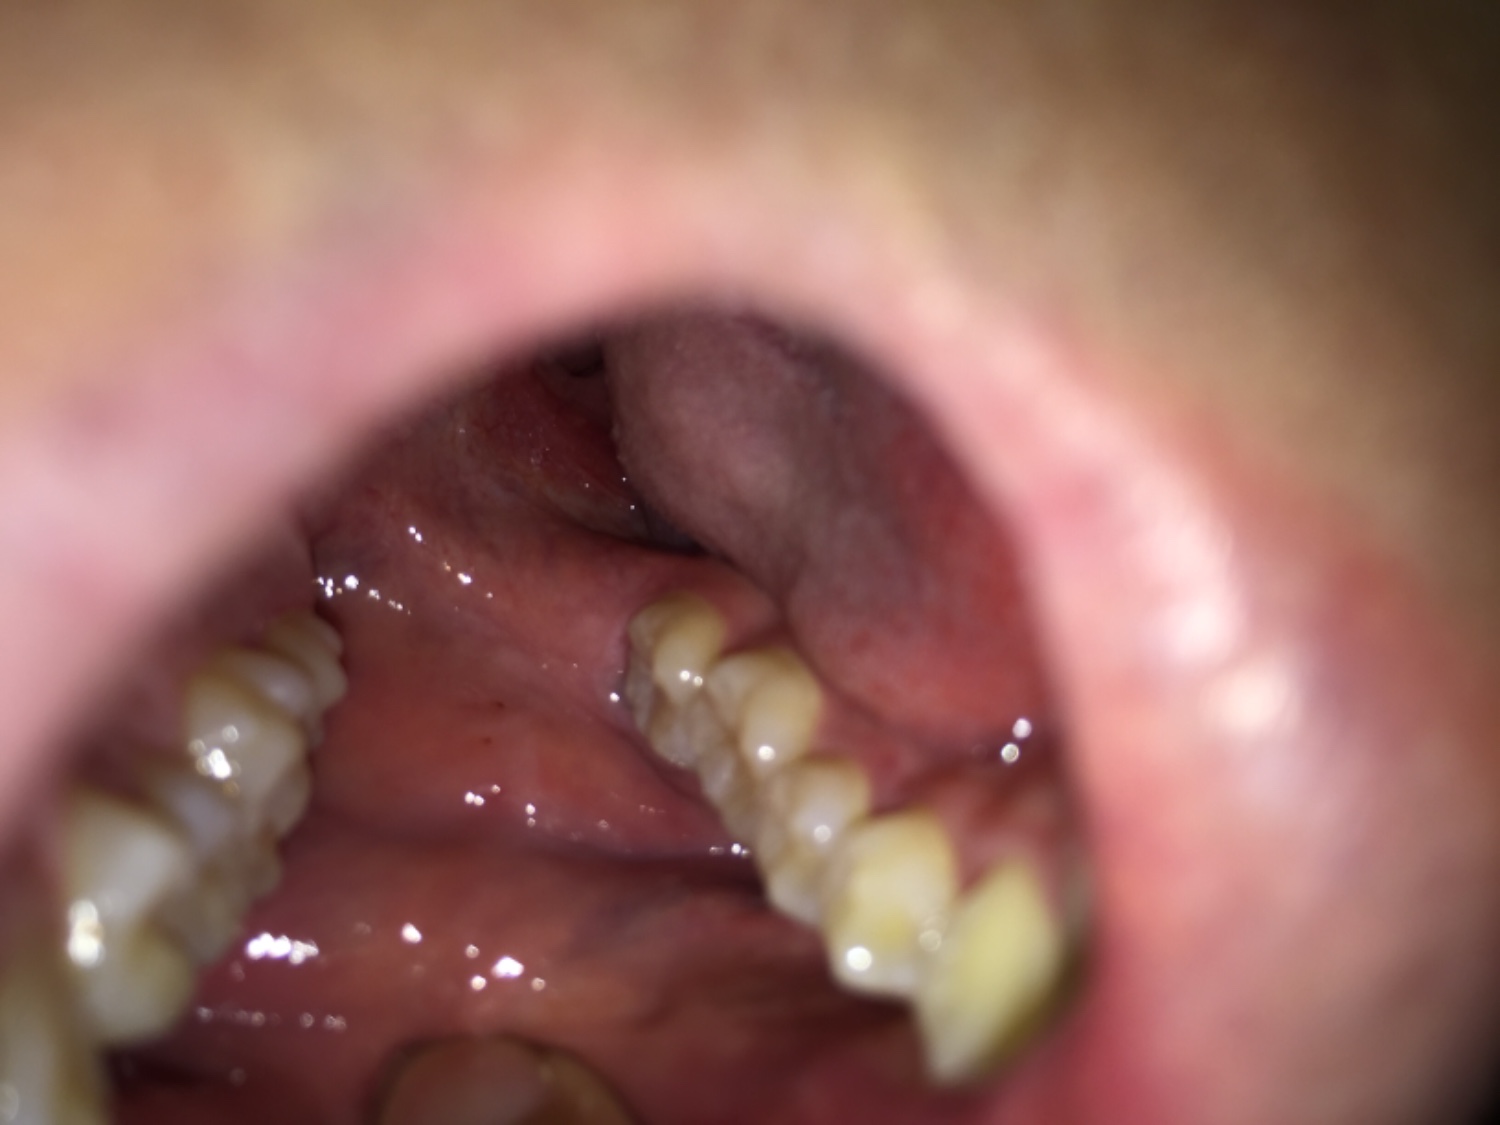

มีจุดเล็กๆขึ้นตรงกระพุ้งแก้มเป็นไรไหมครับ